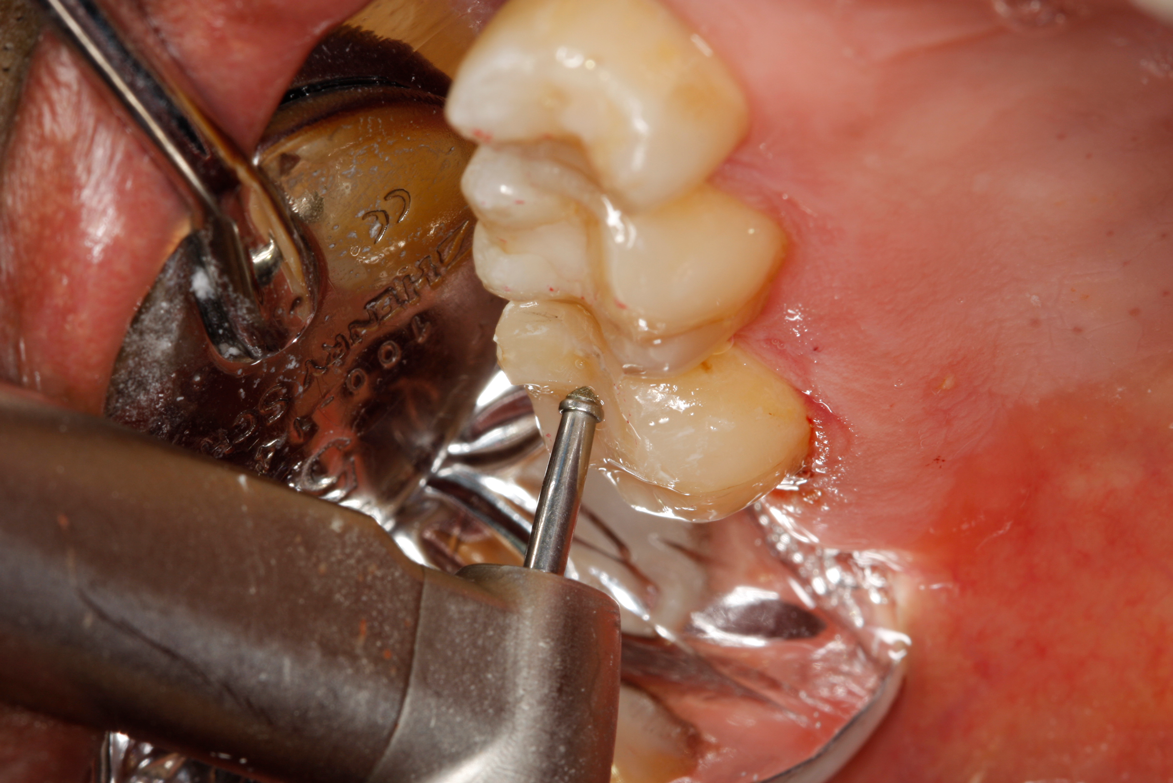

A deep distal occlusal preparation was performed and a matrix band (Paraband, Practicon) was placed again, such that no wedge needed to be placed (Figure 32). The Groman Etchmaster was utilized to remove biofilm as previously shown in Figure 12. A total etch technique with 37% phosphoric acid was employed (Figure 33), and after thorough rinse and damp dry, a universal adhesive (Scotchbond Universal, 3M) with MDP was applied and light-cured 40 seconds at 1,200 mw/cm2 due to the depth of the box form (Fig- ure 34). Figure 35 shows the dual-cure bulk-fill flowable composite (Bulk EZ Plus, Zest Dental Solutions) being injected into the deep box with a 20-gauge bendable needle. It is important to keep extrusion pressure on the plunger while withdrawing the needle to prevent bubbles or voids in the composite interface with the tooth structure. Overfilling by approximately 10% and smoothing the surface only with brushes promotes good marginal seal (Fig- ure 36). It is critical to not disturb the occlusal surface of any dual-cure bulk-fill flowable with an attempt to "soft sculpt," as that may create marginal voids.

Fig 32. Preparation is completed, caries are removed, sand blasting with potassium carbonate is performed, and matrix band is placed.

Figure 32

Fig 33. Total etch with 37% phosphoric acid is performed.

Figure 33

Fig 34. Universal adhesive is applied in total etch technique and is light-cured for 40 seconds due to depth of cavity.

Figure 34

Fig 35. Injection filling of cavity preparation with dual-cure bulk-fill flowable composite to a slight overfill.

Figure 35